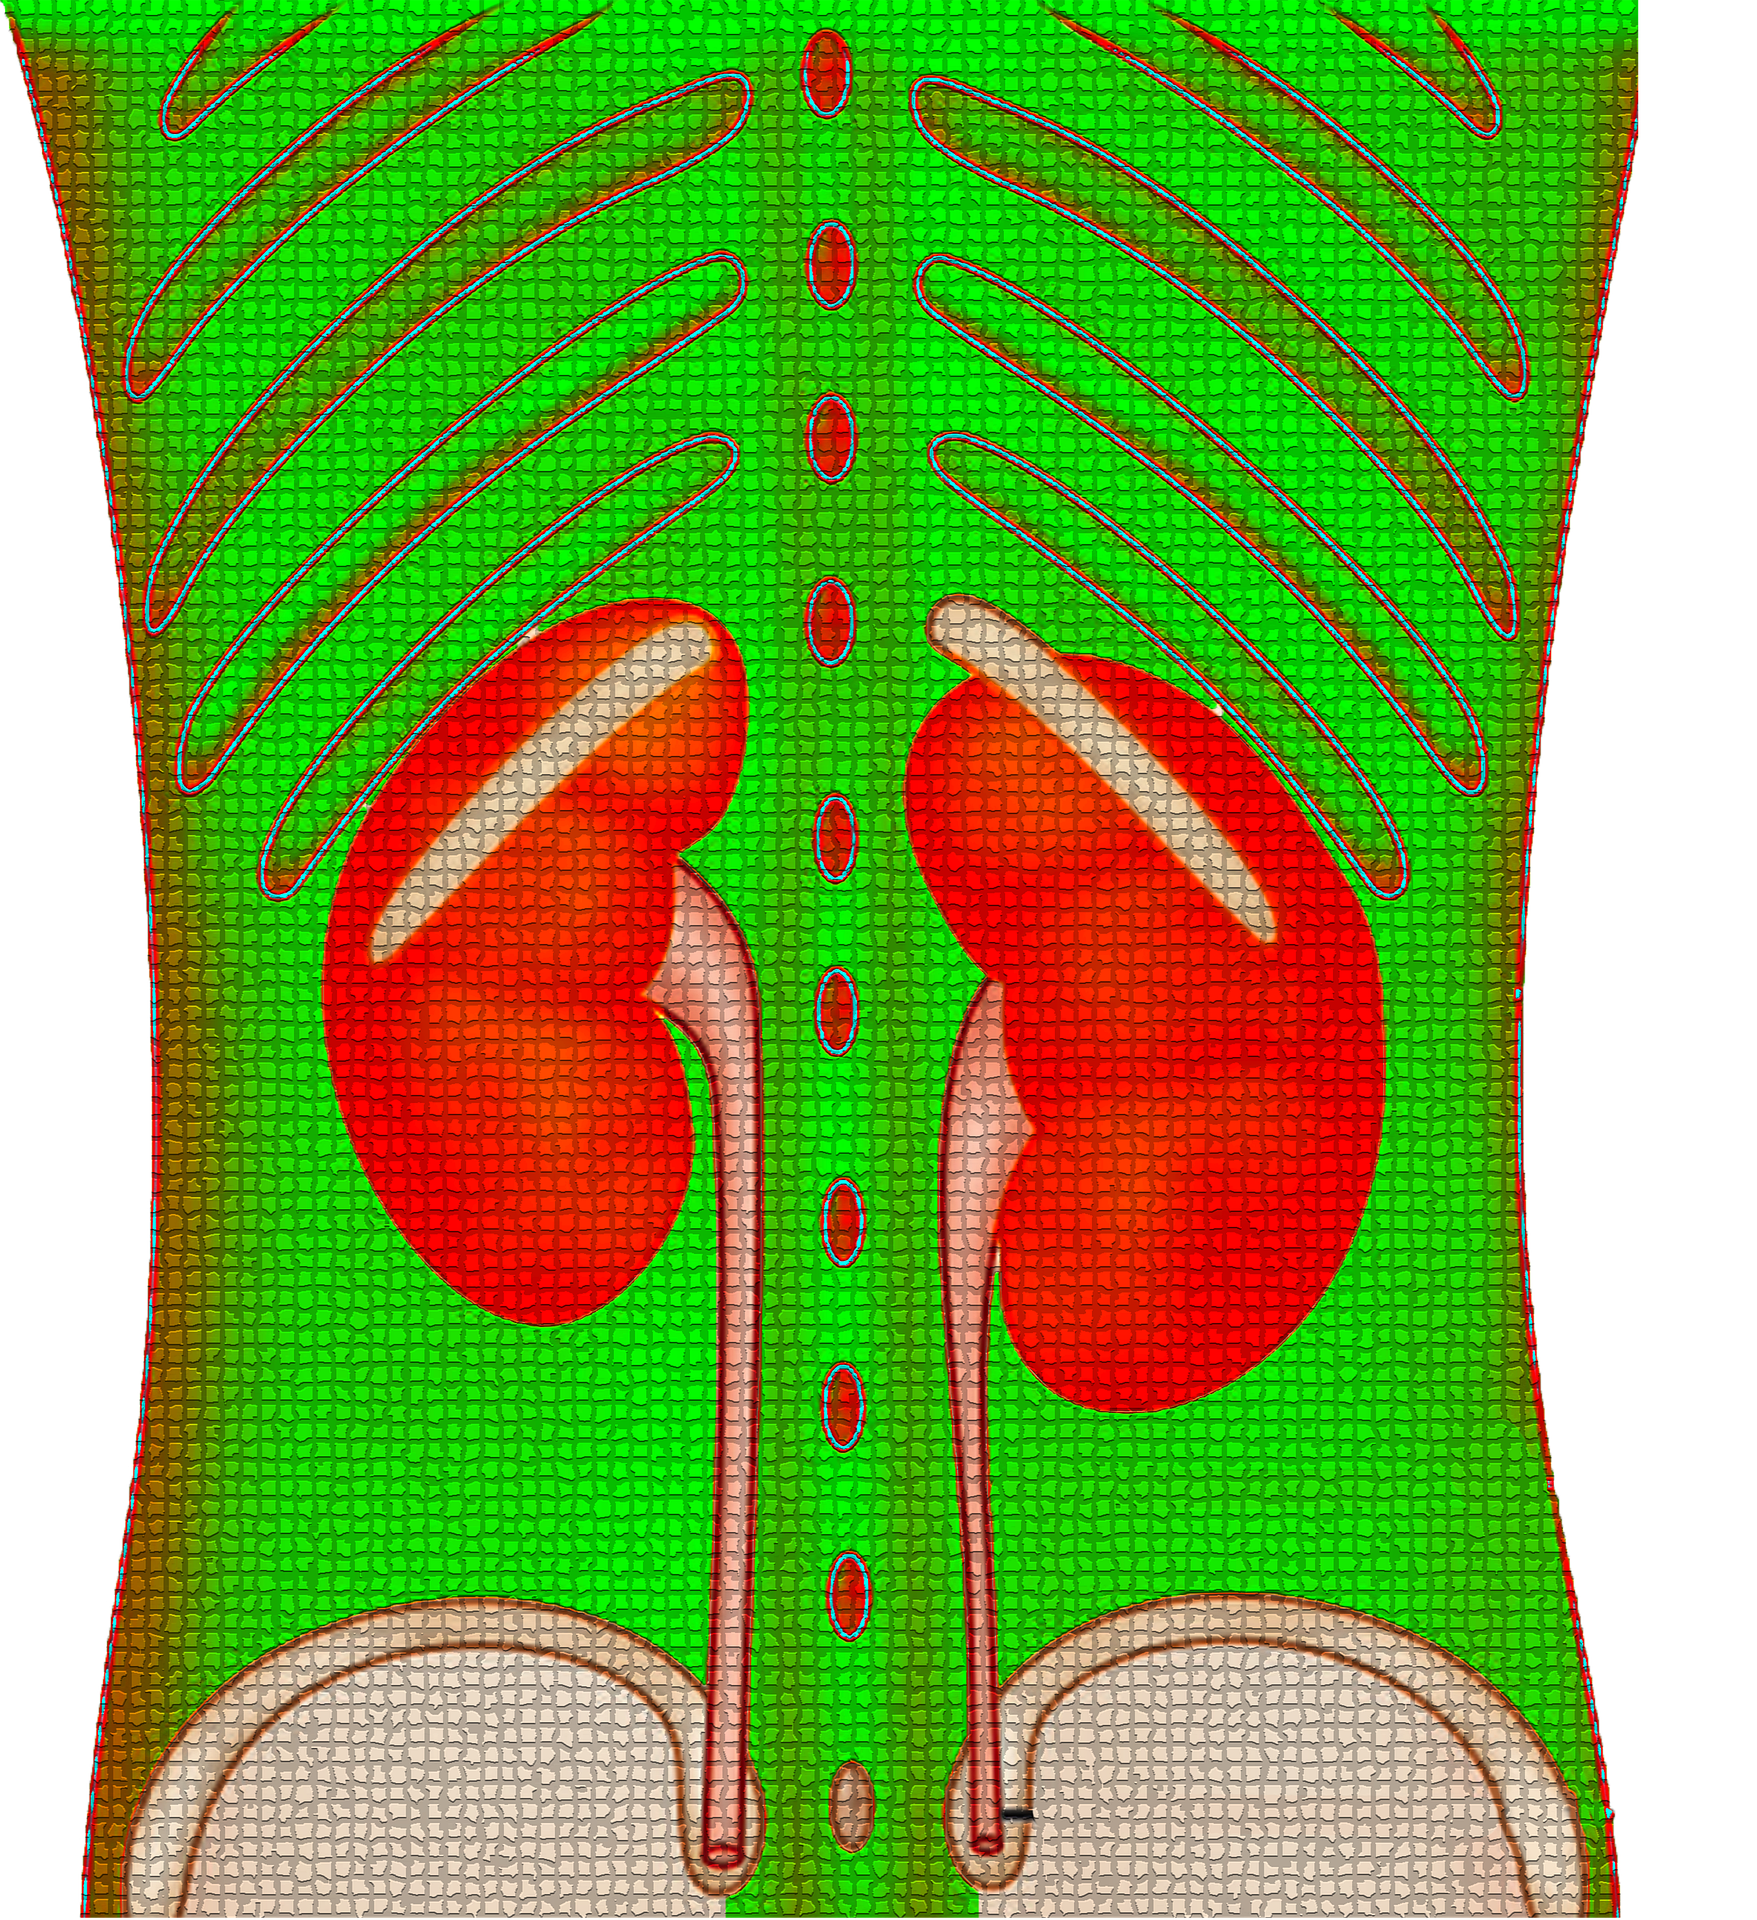

4. 신우신염

신우신염은 신장에 발생하는 질병으로 세균감염으로 많이 발생합니다. 특별한 원인이나 조건없이 발생하는 병적 상태이며, 발열, 오한, 신장주변 압통, 옆구리 통증이 발생하는 경우가 있습니다.

신우신염은 요도의 끝부분 대변이 묻어서 발생하거나 여성의 경우에는 성교시 요로가 손상을 받으며 발생합니다. 치료는 최대 3주일 정도 필요하며 회복후에는 감염 부위에 흉터조직이 형성되지만, 나머지 부분으로도 정상기능을 할 수 있습니다. 만성신우염의 경우는 한쪽만 진행되거나 부분에 국한되면 수술로 어느정도 회복할 수 있습니다.